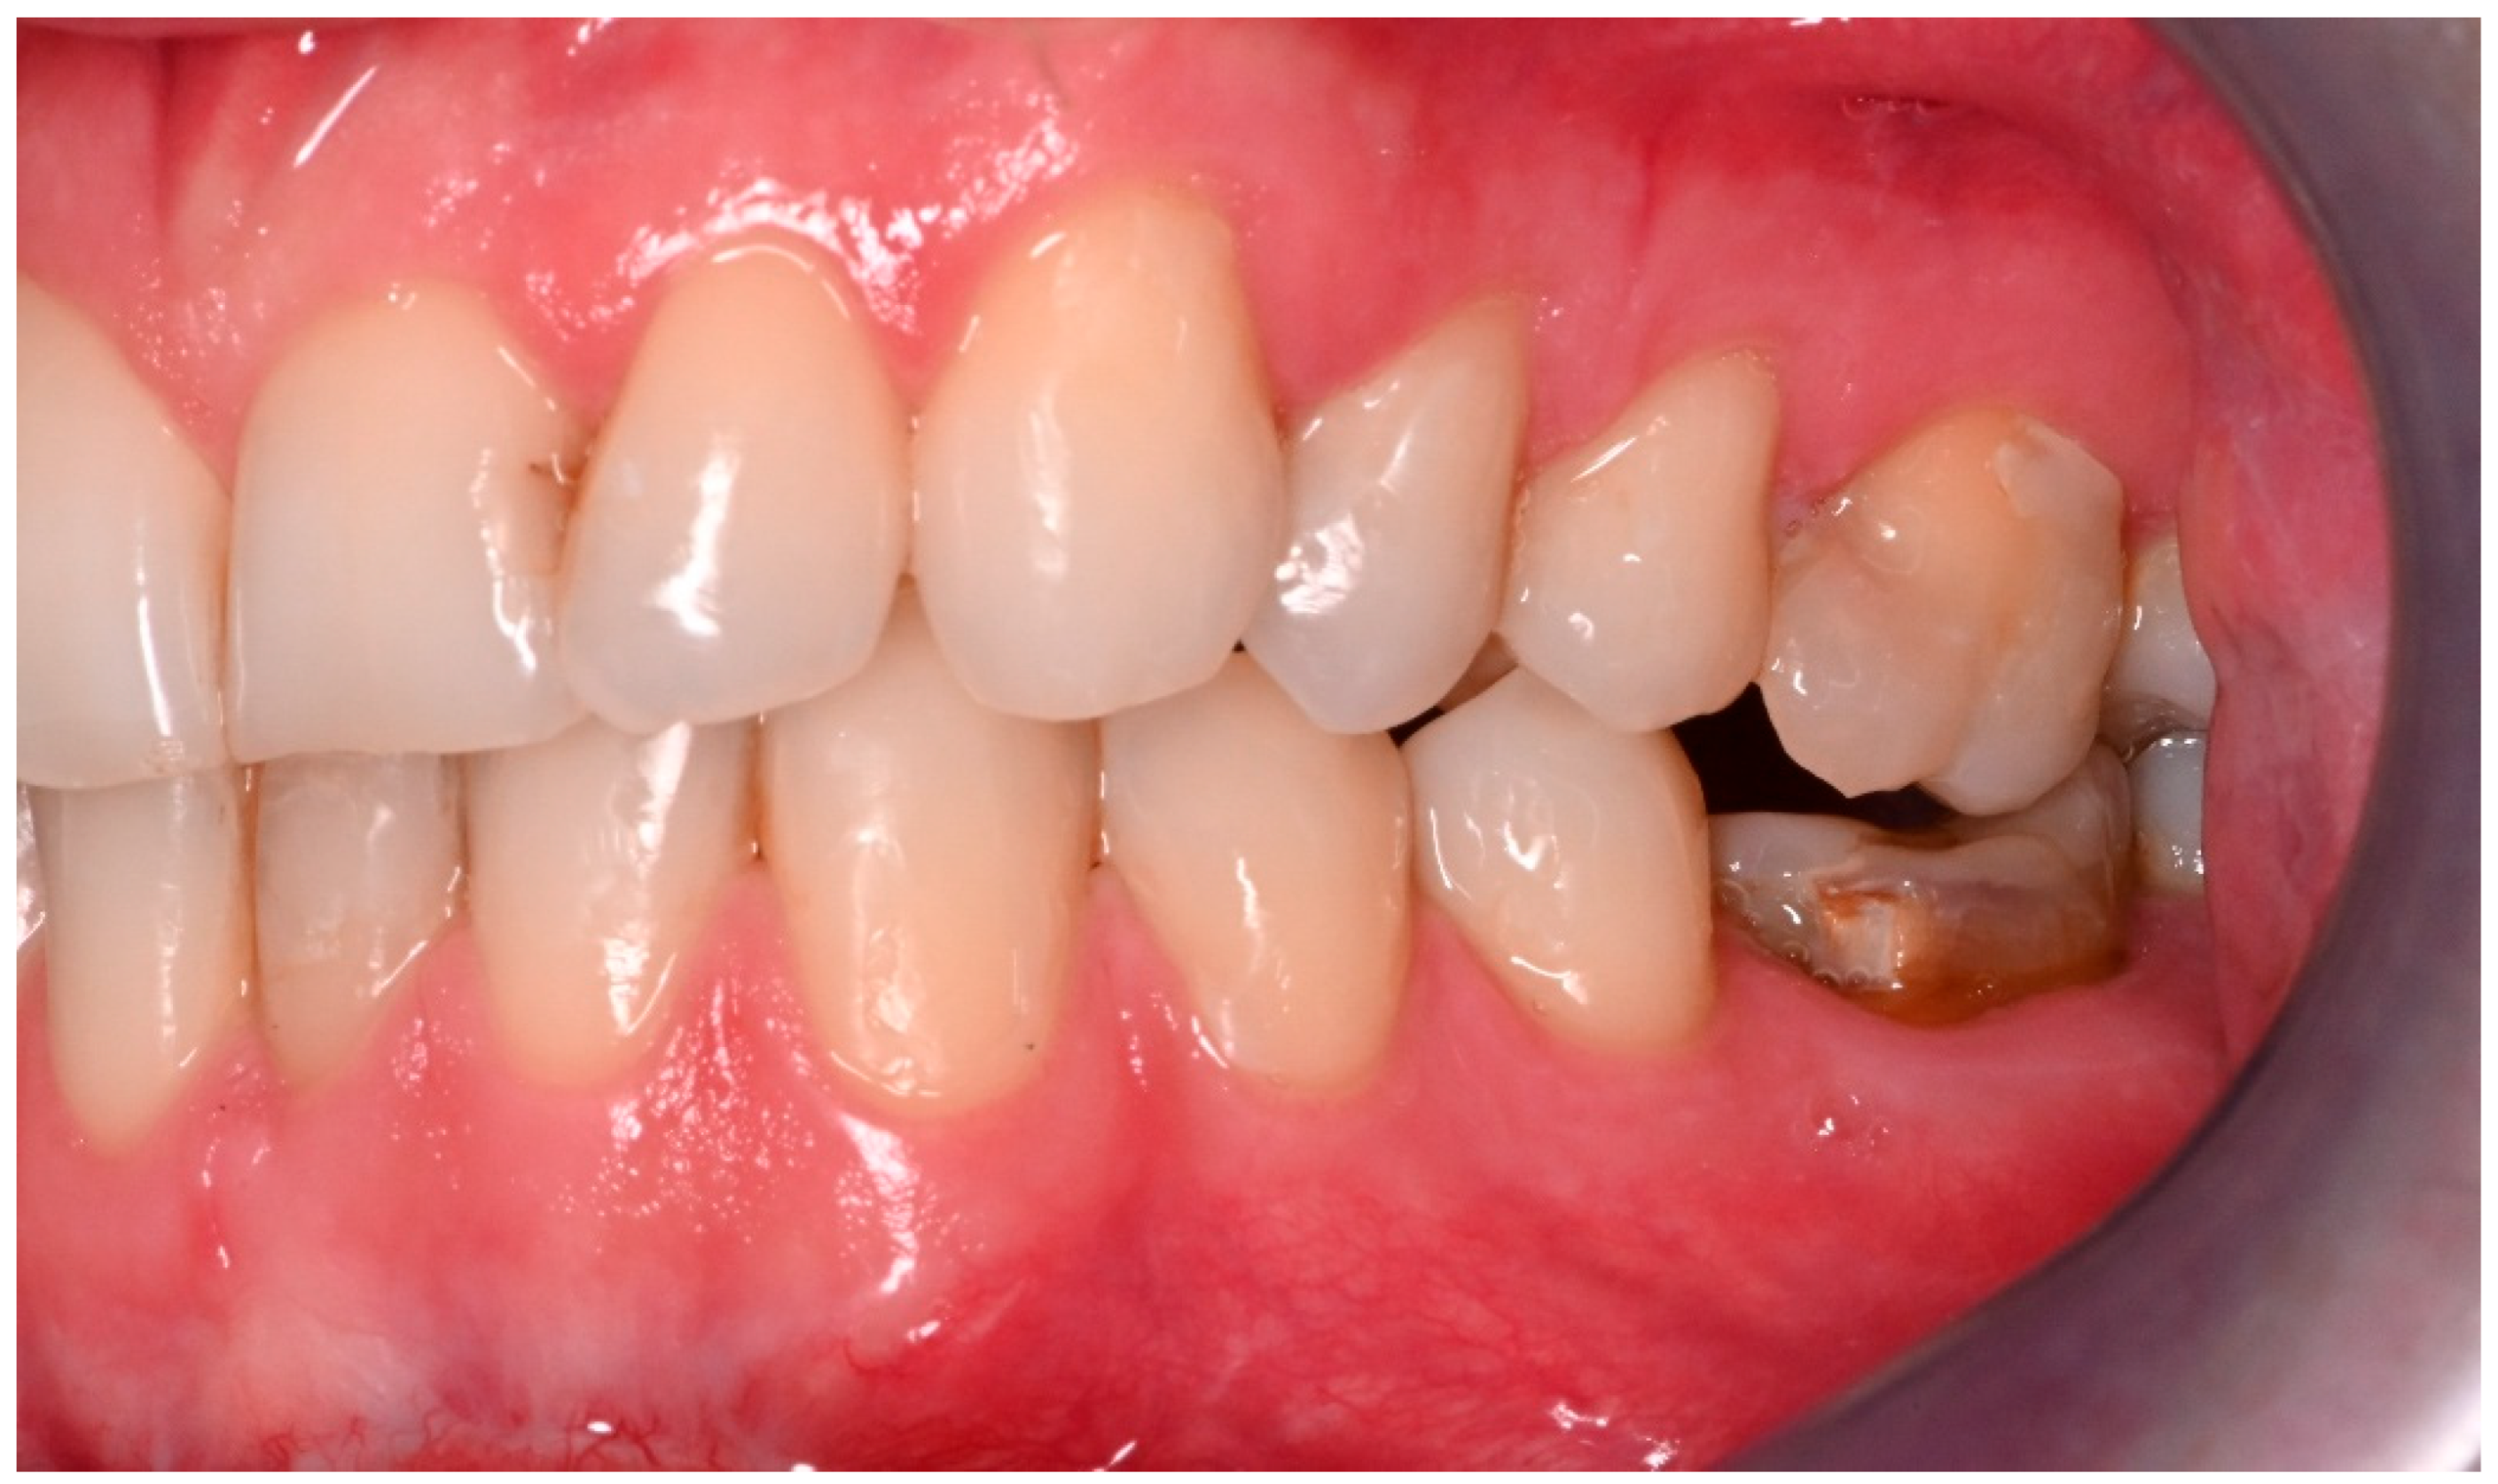

Two operations had to be redone because of inadequate reposition in the symphysis/parasymphysis with broad (>2 mm) lingual splay. In both cases, straight miniplates were removed. Osteosynthesis was achieved with lag screws. Figure 3 depicts plate osteosynthesis of a symphyseal fracture with a broad lingual gap (Figure 3). Figure 4 shows the same patient after redo operation and osteosynthesis of the same fracture with a lag-screw and a marked reduction in the lingual splaying (Figure 4). Figure 5 demonstrates the condylar reduction in the frontal plane in the same patient. Figure 6 and Figure 7 show the patient’s occlusion (Figure 5, Figure 6 and Figure 7). The third redo operation was due to nonunion and infection of an angular fracture with fracture of the two condylar plates. In this case, after removal of the infected miniplate, the angle fracture was stabilized with a reconstruction plate and a miniplate from an extraoral approach; the two broken miniplates at the condylar process were left in situ.

Figure 6. Inadequate occlusion with crossbite on the right-hand side after insufficient reduction in the condylar neck on the same side (see Figure 5).

Jcm 14 07142 g006

Figure 7. Adequate occlusion on the left-hand side, after satisfactory reduction in the condylar neck on the same side. The lower molar crown was fractured in the accident (see Figure 5).

Jcm 14 07142 g007